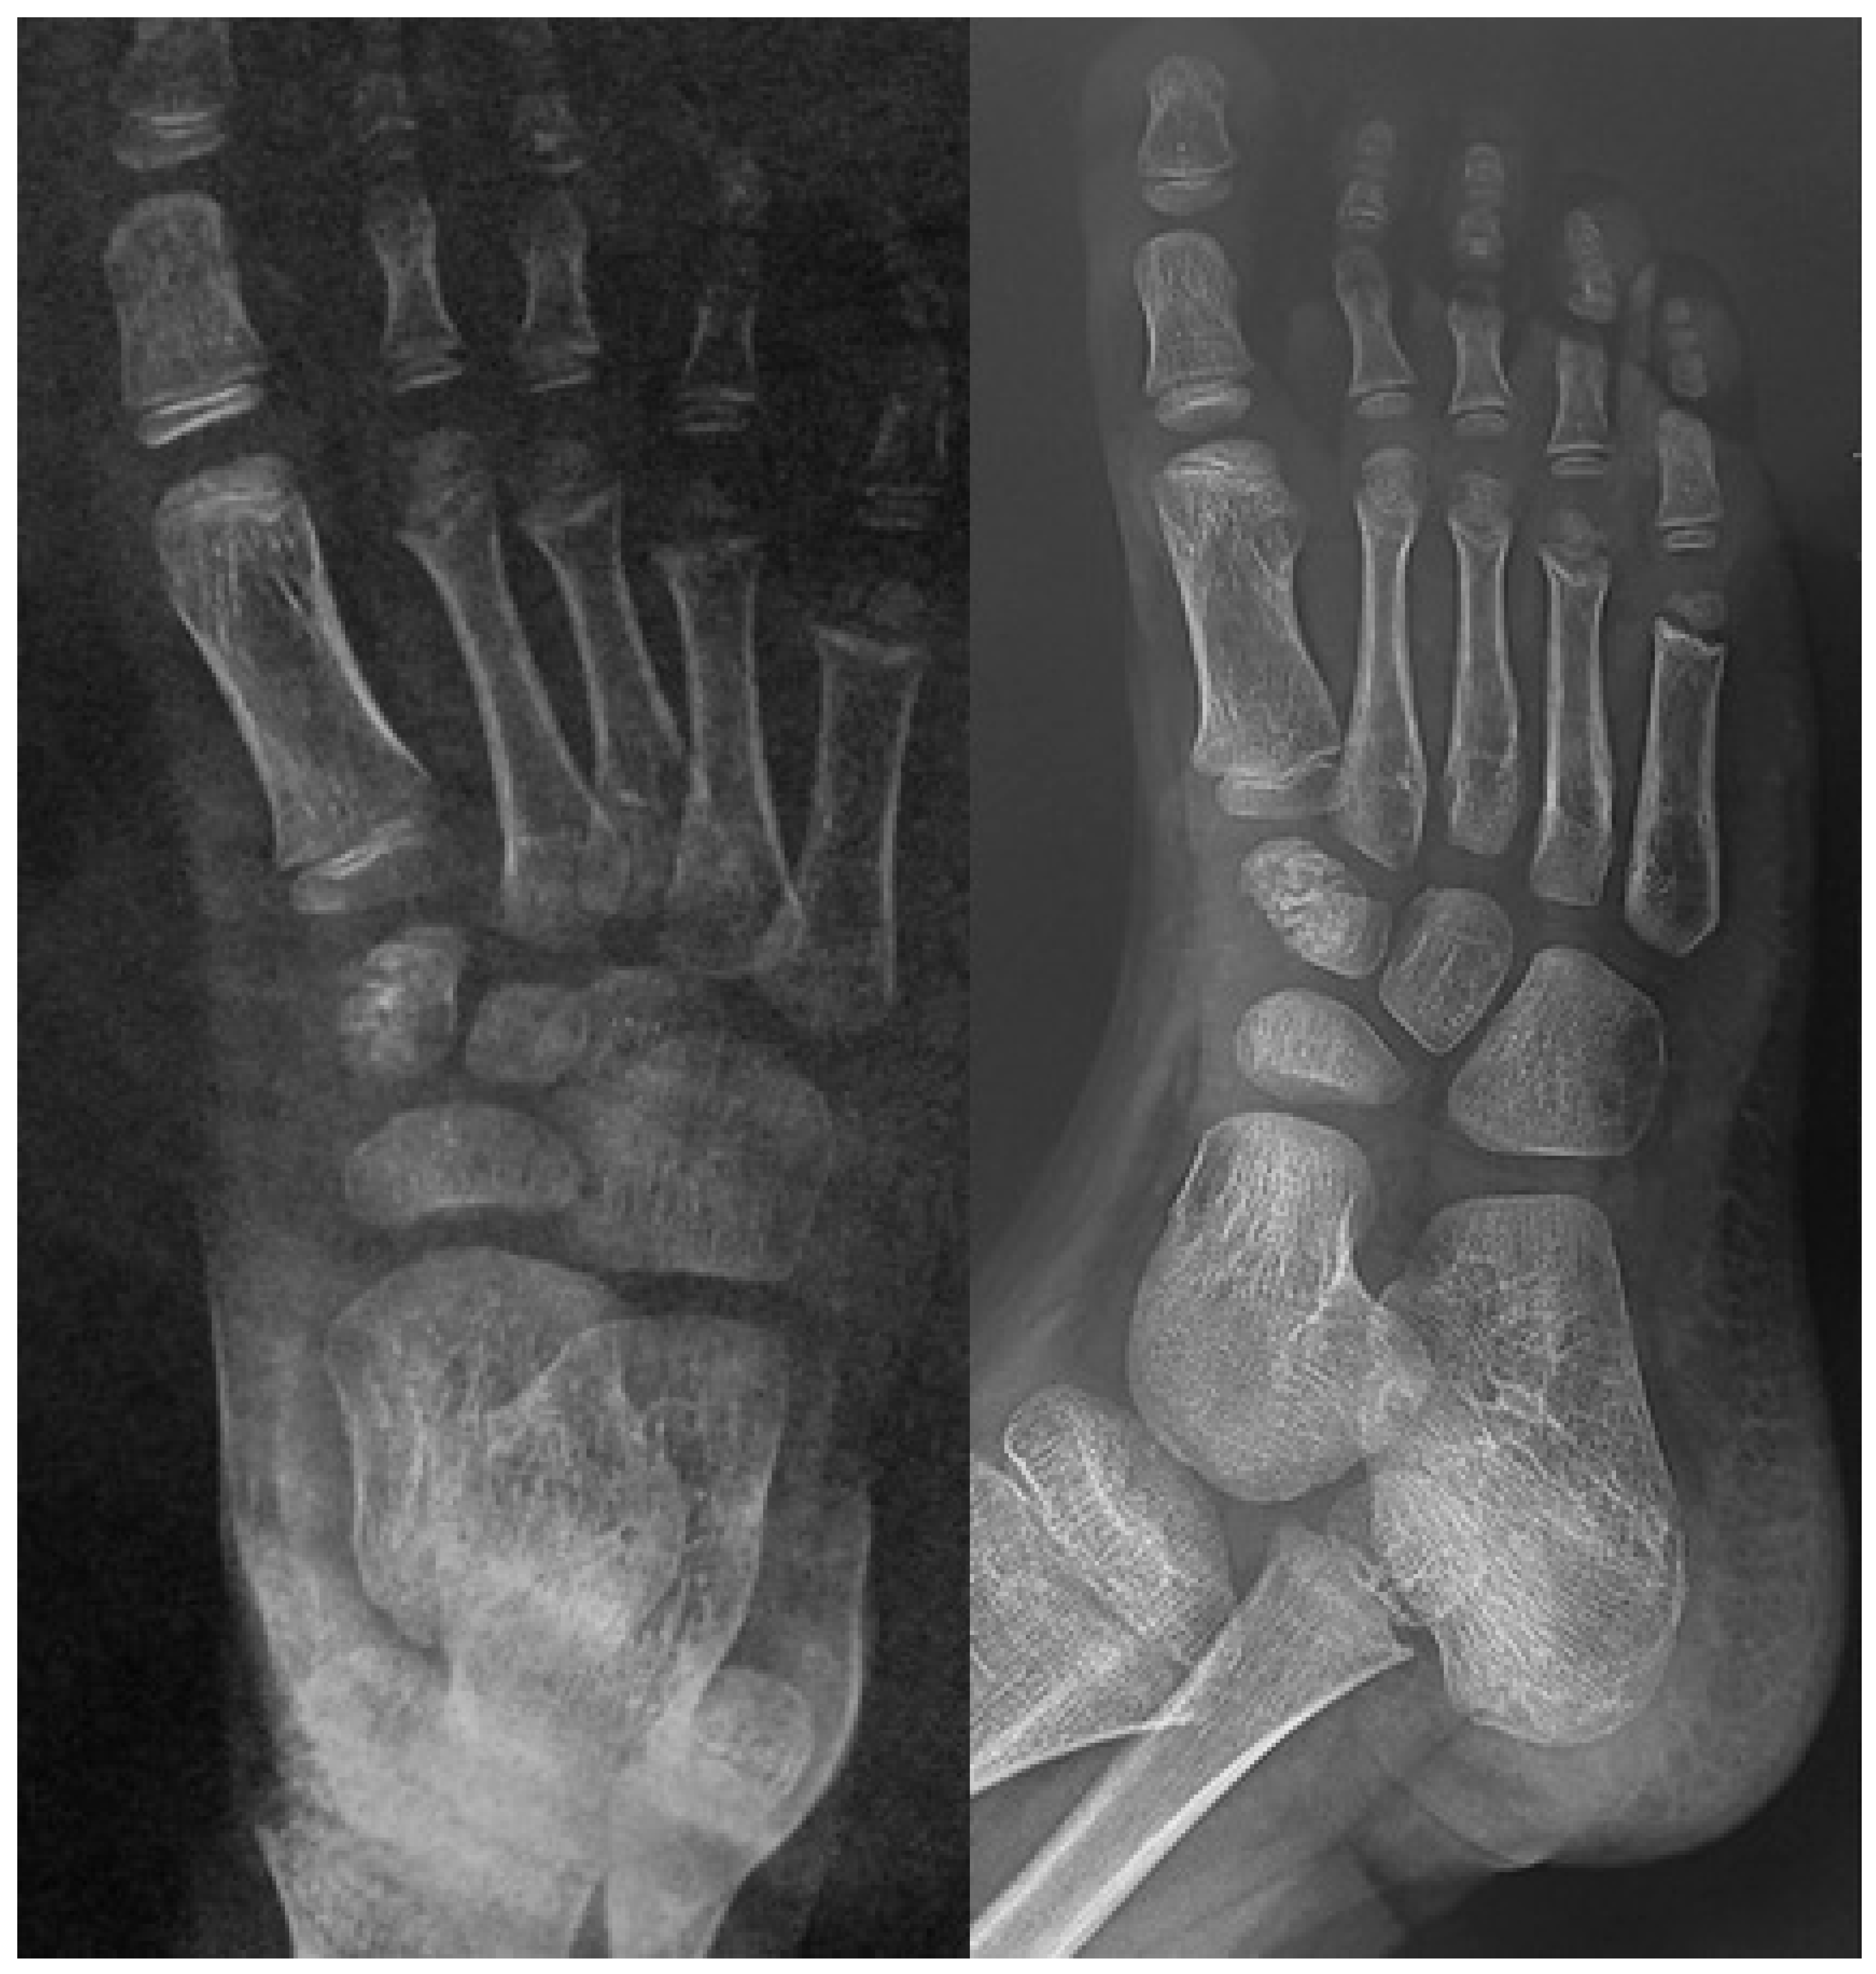

If not promptly identified and adequately treated, the condition may progress to severe deformities in adulthood (Figure 13).

Figure 13.

The radiographic progression of the second metatarsal head osteochondrosis in a 22-year-old female patient who had not received any treatment.